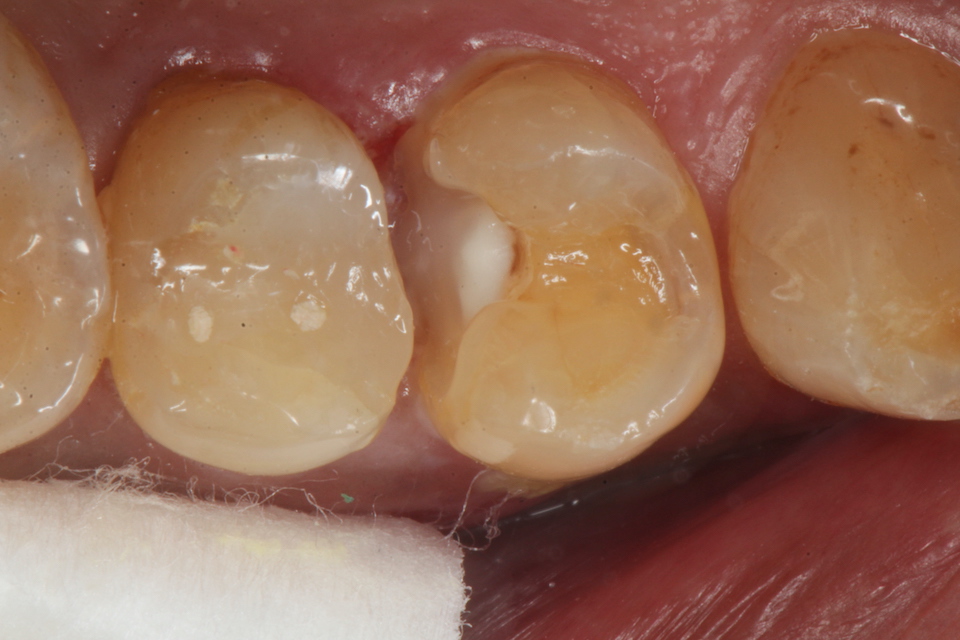

50代男性、右上45、インレー破折後の2次カリエス、咬合性外傷

露髄ギリギリなのだが、自覚症状はない。虫歯がある程度進むと染みたり痛みを感じにくくなる。それは虫歯は水素イオンの電導性がないからだ。水素イオンが歯髄の神経に到達すると痛みを感じるのだが、水素イオンの伝導は歯の主成分のハイドロキシアパタイトだけにしか起こらず、ハイドロキシアパタイトが壊れてしまった虫歯には水素イオンが伝導しない。